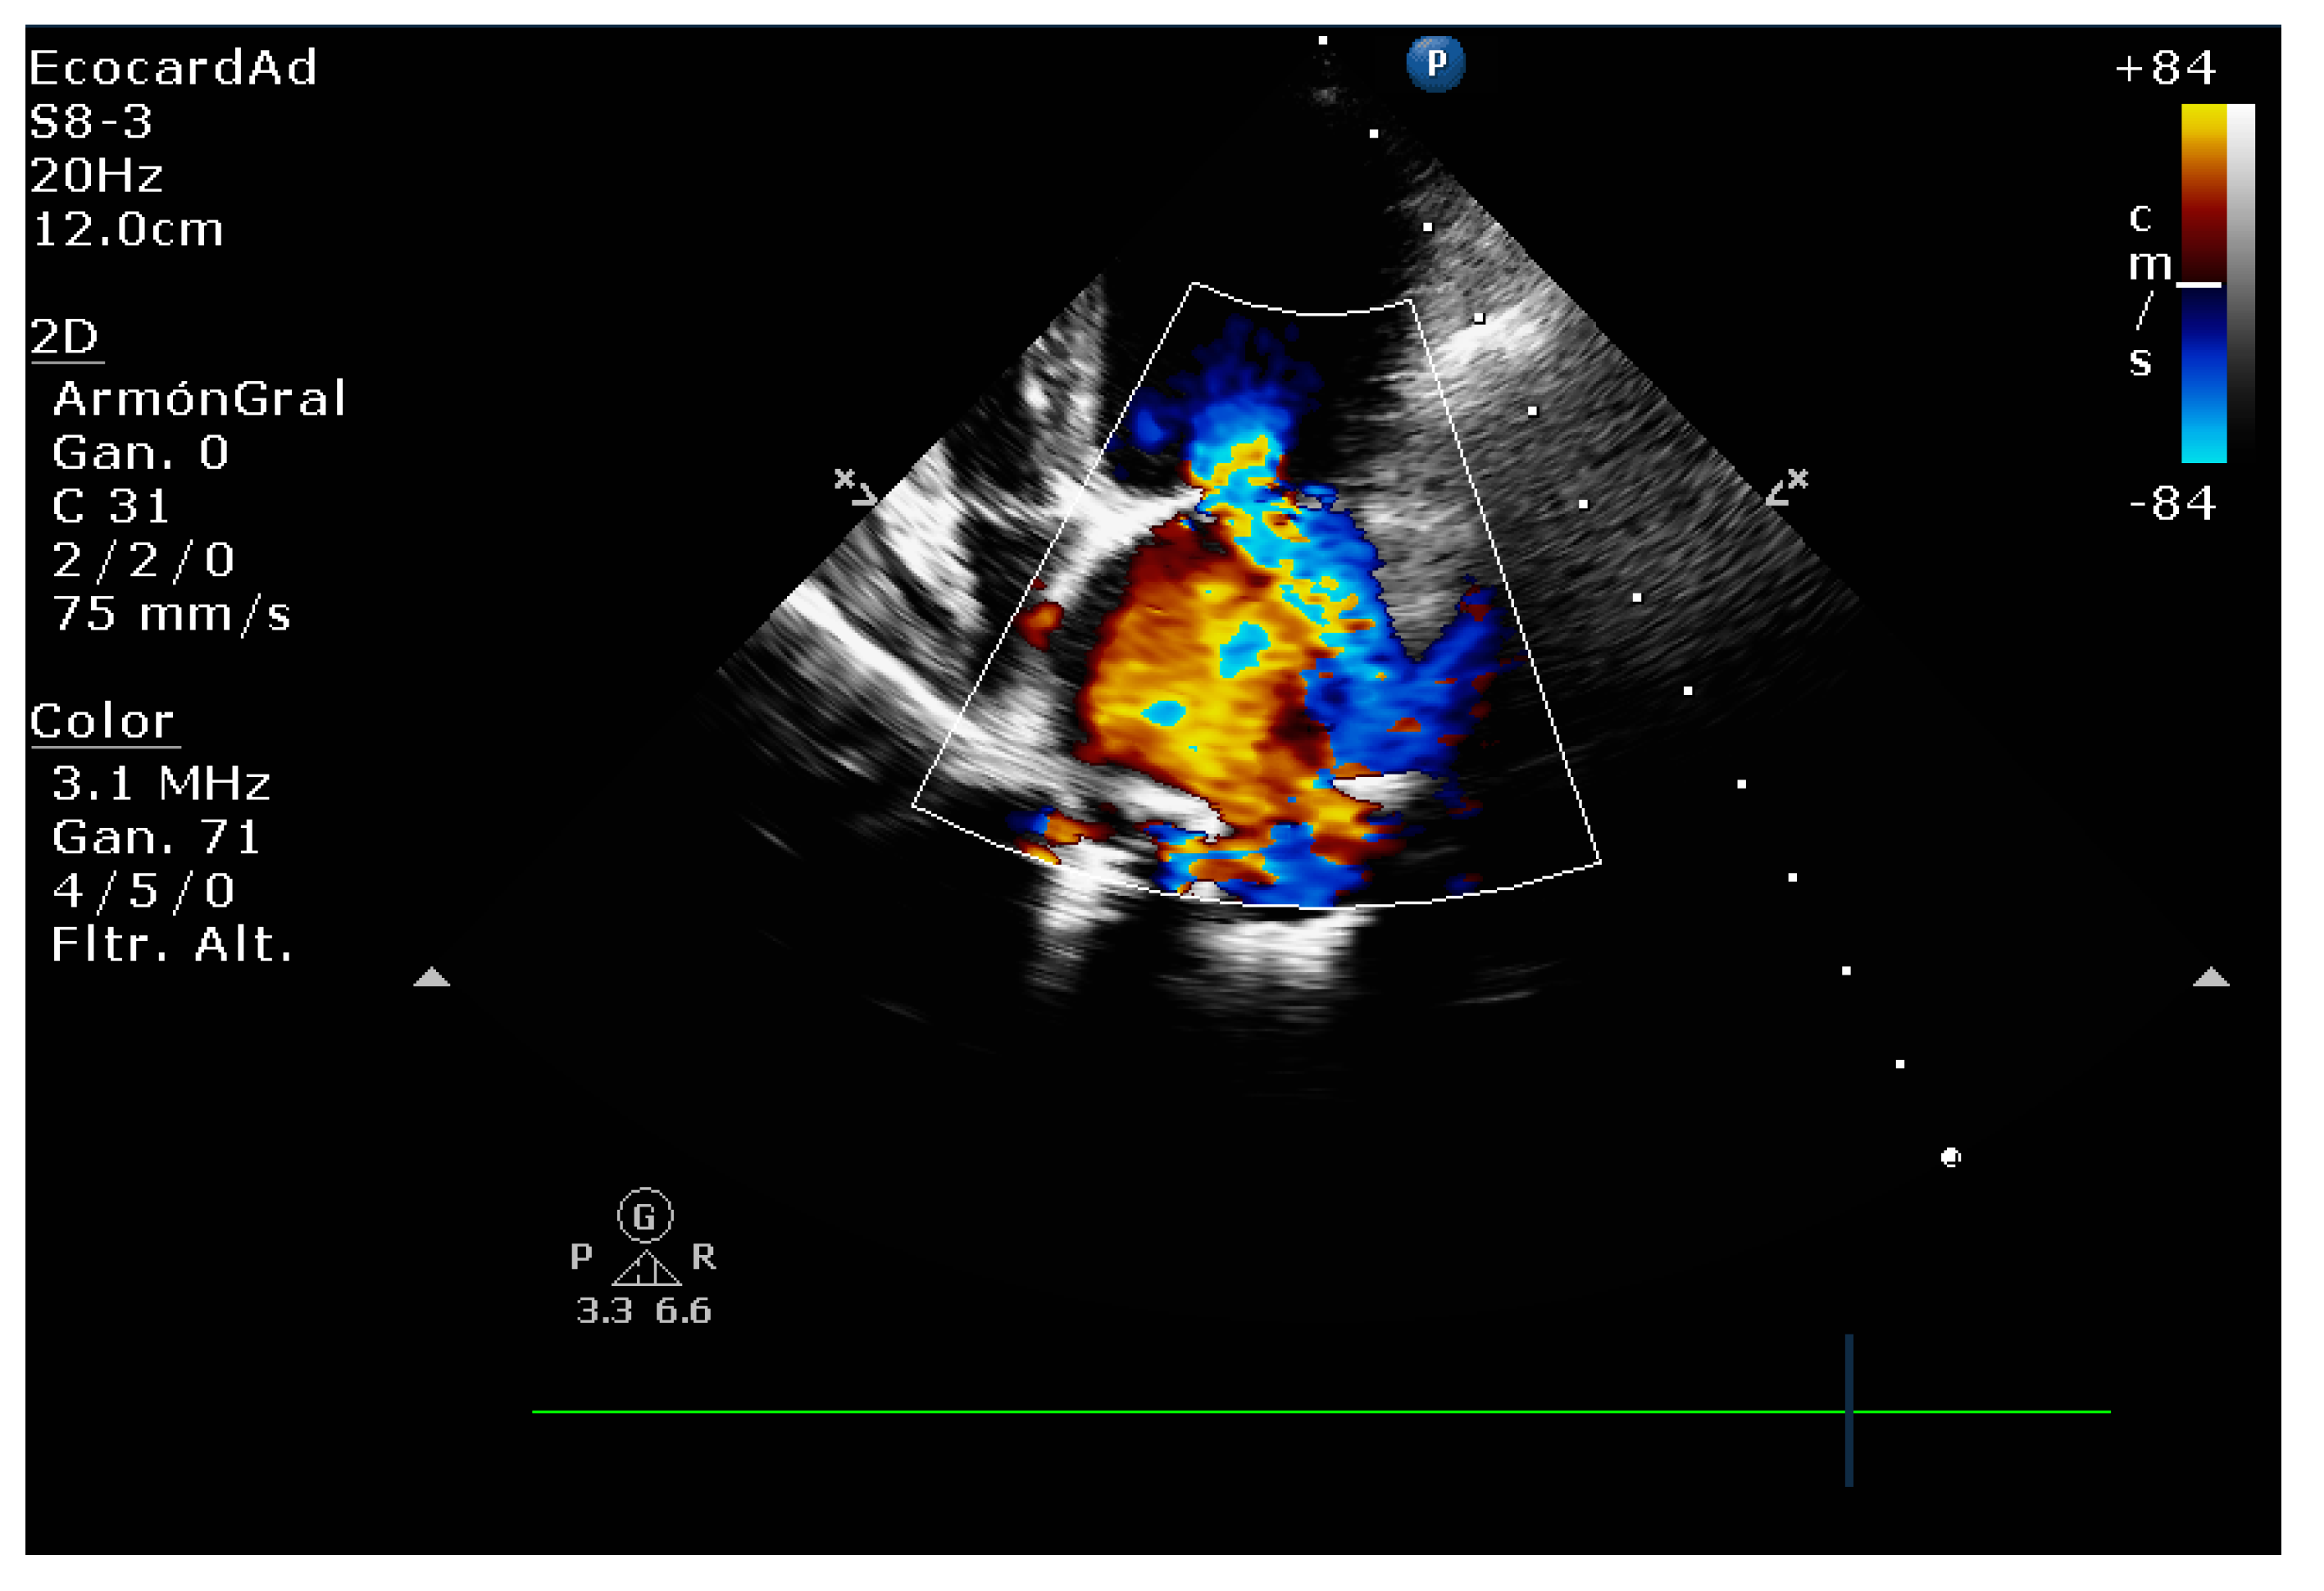

4.4. Comparative Assessment of Mitral Regurgitation Severity

4.5. Mitral Regurgitation Quantification in the Canine Model

4.8.1. Evaluation of the Regurgitant Area

4.8.2. Presence of Vena Contracta

| Color flow imaging of the mitral regurgitation jet area | The most commonly used technique for assessing severity in dogs. The former method is not used in humans as it is not considered reliable for determining the severity of mitral insufficiency. |